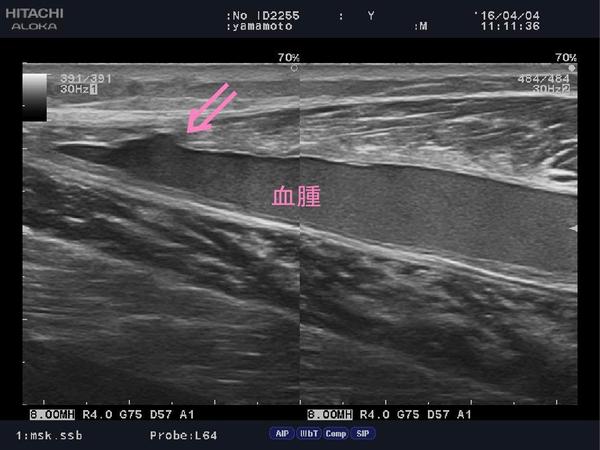

本日二枚の写真、両方とも「ふくらはぎの肉離れ」

1枚目は受傷後1ヶ月。

ピンクの矢印部分、筋繊維の断裂部分が、

バッチリ写っとります。

受傷後から整形外科に通われていたのですが、

なかなか痛みが取れないと御来院。

画像で確認してみると、断裂部分もまだまだ、

血腫が大きく出ちゃってます。